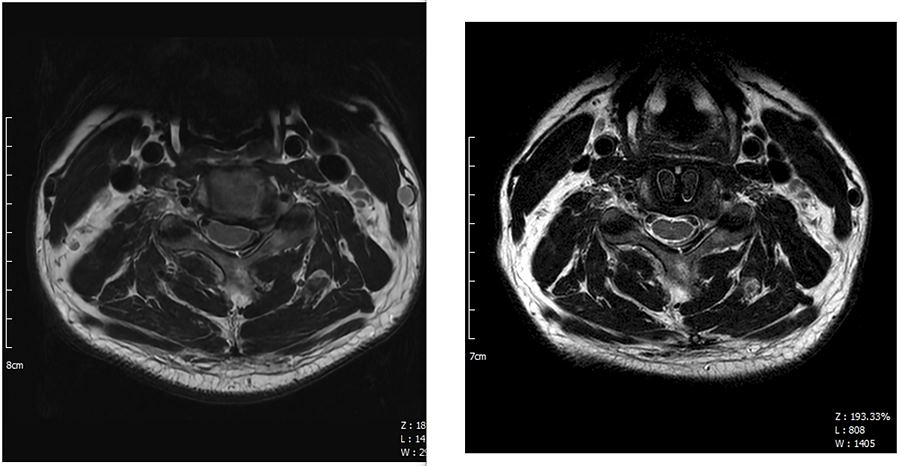

3. X-Ray 세로 사진 : 오른쪽이 수술 후

. 신경공을 더 넓히지는 못했지만 케이지를 넣음으로써 분절간 높이가 수술 전보다 확연히 높아졌다.

. 교수님도 분절 사이가 높아졌으니 그만큼 공간이 더 생겼고 크게 걱정하지 않아도 된다고 하셨다.